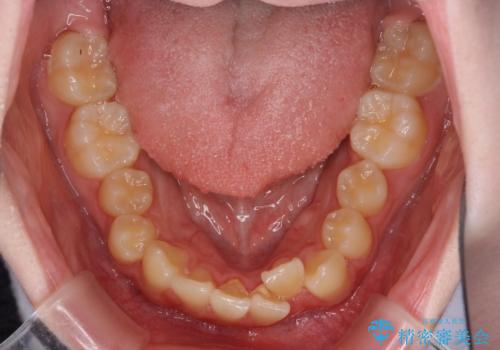

- 上下前歯のデコボコを気にして来院された患者様です。

前歯の叢生は強かったのですが、口元が引っ込んでいる印象であったため、非抜歯にて矯正治療を行うこととしました。

インビザラインでの自己管理は難しいとのことで、ワイヤー装置にて矯正を行うこととしました。